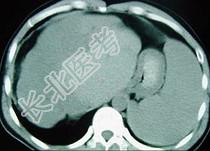

- 单项选择题女性,72岁, 腹胀不适1年,加重伴恶心、呕吐、乏力1个月, 影像检查如图,最可能的诊断为  (    )

- A、肝硬化腹水

- B、原发性肝癌

- C、肝血管瘤

- D、巴-希综合征

- E、局灶脂肪肝